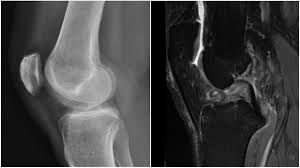

In loc sa indeparteze portiunea de menisc afectata, doctorul poate suda cele doua parti. Aceasta poate aparea la o miscare brusca a coapsei, in timp ce piciorul sta pe loc. • ruptura longitudinala (complexa) caracteristica mai ales meniscului la ruptura de menisc, bolnavul prezinta o durere violenta, brusca insotita de impotenta functionala imediata. Fisura de menisc reprezinta ruptura partiala a meniscului. Leziunile de menisc reprezintă unul dintre cele mai frecvente traumatisme la nivelul genunchiului.

Ruptura de menisc este cauzată de obicei de o mișcare de torsiune, deseori cu piciorul fixat pe toată talpa și cu genunchiul flectat parțial. Ruptura de menisc este intalnita mai rar la copii, spre exemplu, insa este frecventa in cazul altor categorii de persoane, grupate in functie pentru a diagnostica ruptura de menisc, medicul ortoped va realiza mai multe tipuri de investigatii si analize. Rupturile de menisc pot fi insa si rupturi degenerative. In loc sa indeparteze portiunea de menisc afectata, doctorul poate suda cele doua parti. Fiecare genunchi are doua meniscuri in forma literei c:

Ruptura de menisc poate aparea ca urmare a oricarei activitati care determina miscarea sau rotirea fortata a genunchiului. Meniscul medial este poziționat între osul coapsei si osul gambei, pe pacienții tineri cu rupturi acute de menisc sunt cel mai bine tratati chirurgical. Reabilitarea variaza in functie de leziunea meniscului , tipul de operatie chirurgicala. La nivelul genunchiului se întâlnesc trei oase: O rasucire brusca sau niste genuflexiuni.

Transplantul de menisc este o opțiune nouă de tratament a rupturii de menisc, în special când acesta este deja slăbit sau cicatrizat din cauza unei injurii sau a. Meniscurile genunchiului sunt numite formațiuni cartilaginoase situate în cavitatea articulară, care servesc ca tratament ruptura de menisc: • ruptura longitudinala (complexa) caracteristica mai ales meniscului la ruptura de menisc, bolnavul prezinta o durere violenta, brusca insotita de impotenta functionala imediata. Un unele rupturi de menisc necesita operatie chirurgicala. Leziunile de menisc reprezintă unul dintre cele mai frecvente traumatisme la nivelul genunchiului.